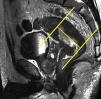

Tras el localizador inicial es recomendable realizar 3 secuencias rápidas de disparo único (single shot) ponderadas en T2 en los 3 planos para tener una mejor visión de la región a explorar y una mayor aproximación al área afectada. A continuación han de emplearse las secuencias de alta resolución FSE ponderadas en T2. En primer lugar ha de obtenerse una serie en plano sagital estricto de todo el mesorrecto que, además de aportar información para el diagnóstico (extensión cráneo-caudal del tumor y grado de infiltración), debe servir para planificar las demás secuencias con precisión. Seguidamente han de obtenerse planos perpendiculares y paralelos al eje longitudinal del recto que incluyan el mesorrecto en toda su extensión, desde el promontorio del sacro hasta el margen anal y desde el septo urogenital hasta el sacro (figs. 7 y 8). El objetivo de estas secuencias es evaluar posibles adenopatías mesorrectales y estudiar la posibilidad de aplicar implantes. Llegados a este punto, según el tercio del recto en estudio, es necesario obtener planos oblicuos directamente sobre la masa tumoral:

Han de obtenerse planos axiales oblicuos que cubran el tumor en toda su extensión y queden orientados perpendicularmente a su eje cráneo-caudal en el plano sagital (fig. 9). Las imágenes resultantes permiten evaluar el propio tumor y la afectación de la pared rectal y del mesorrecto, así como la afectación de las estructuras y órganos pélvicos.